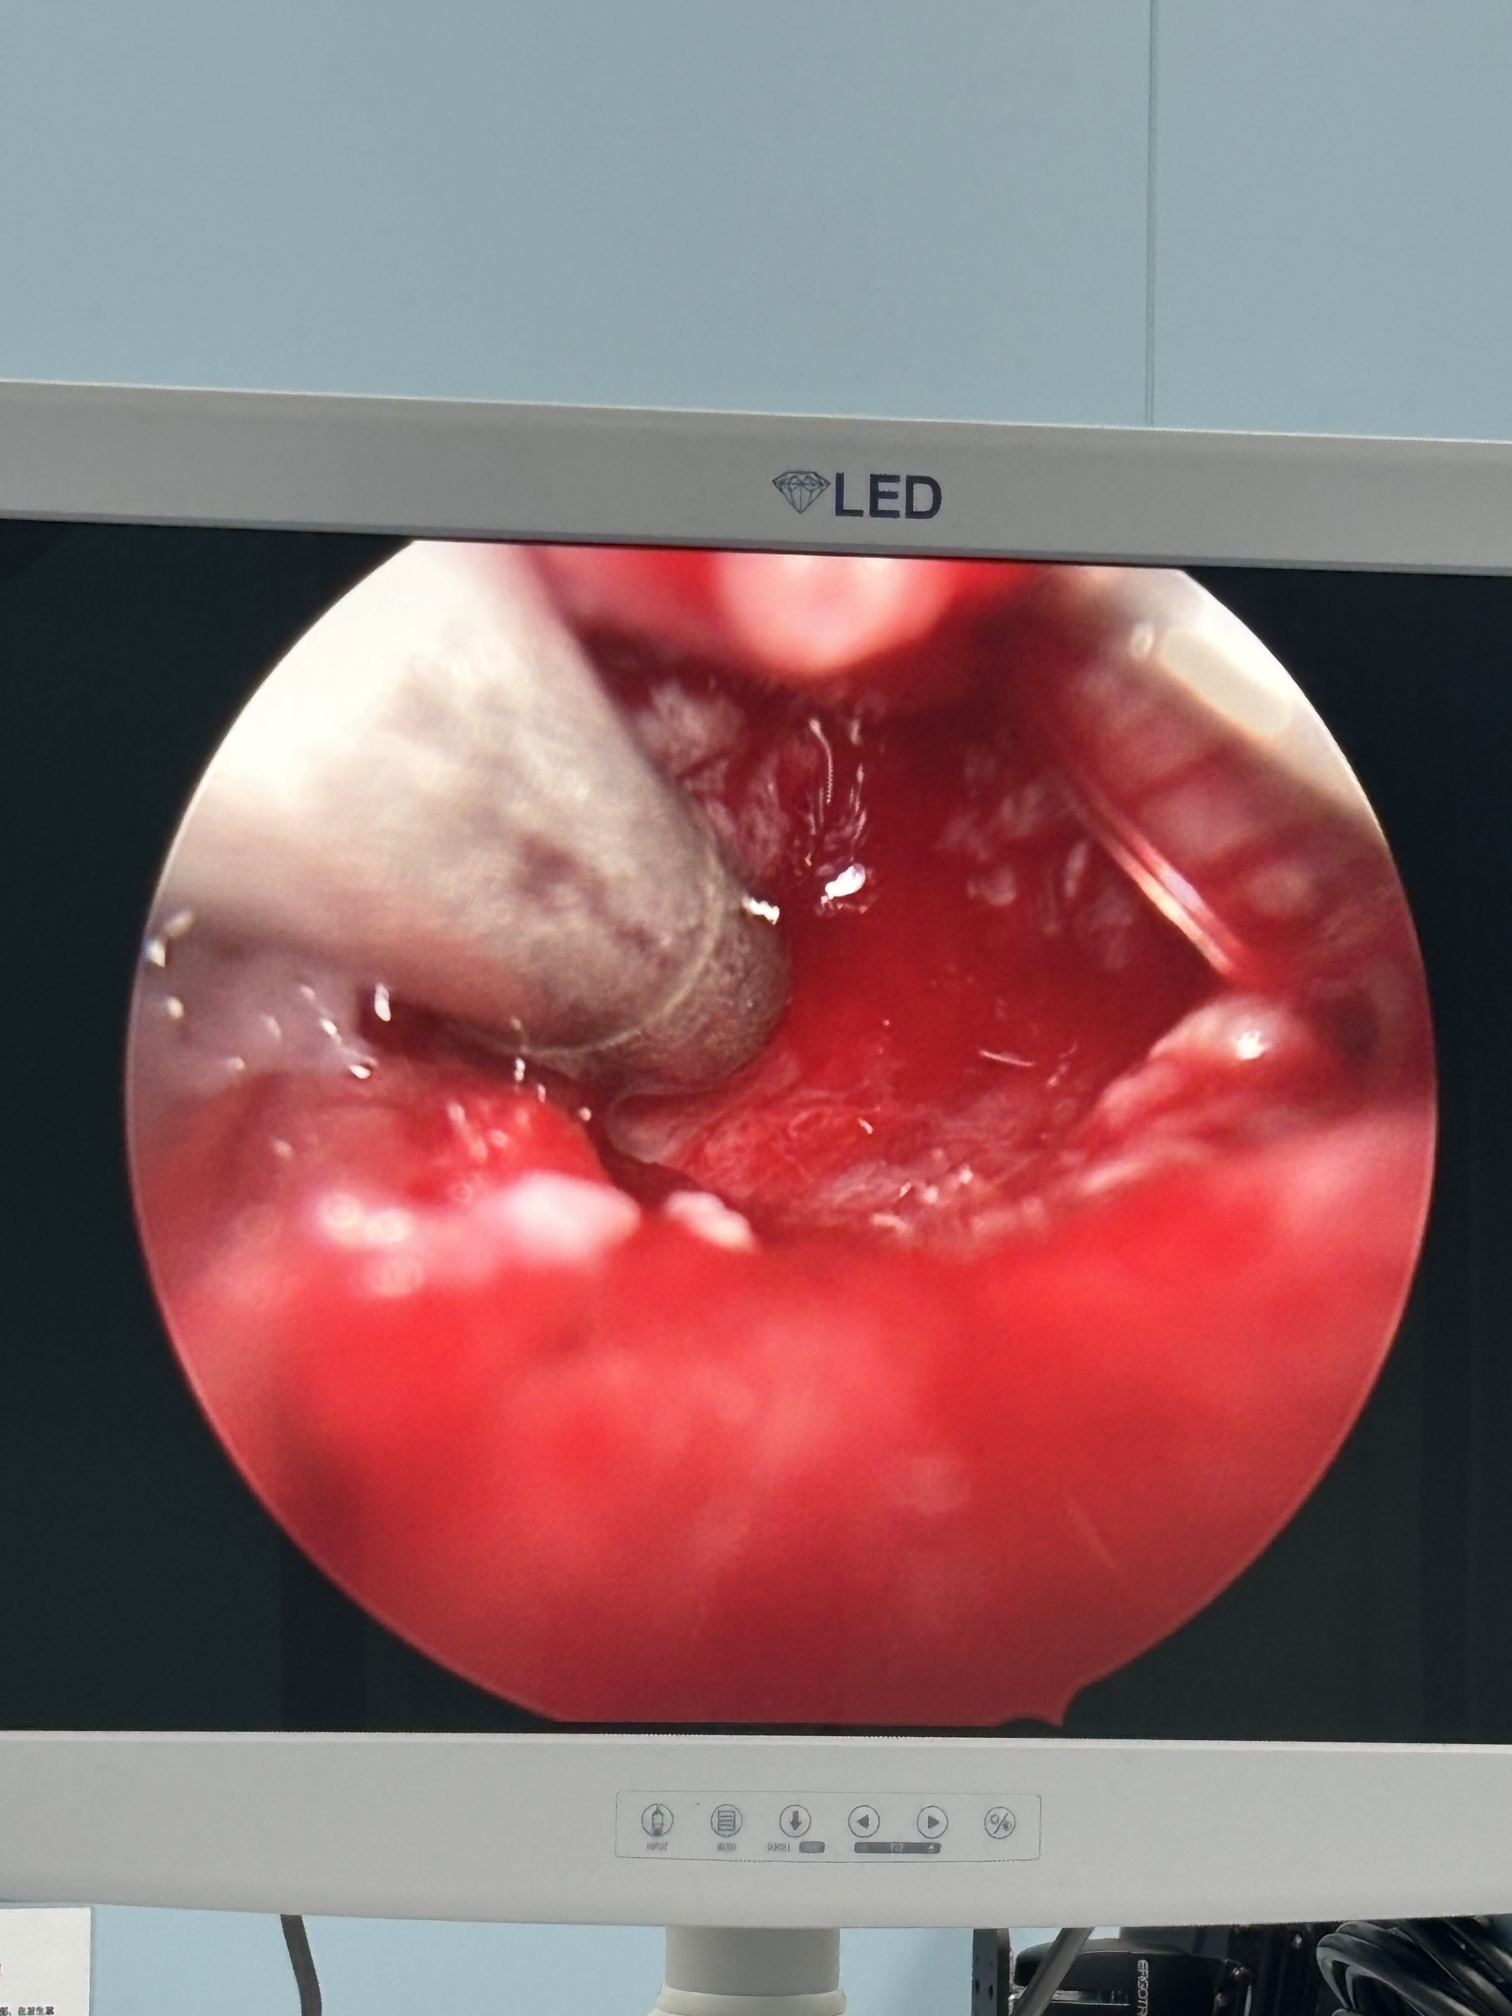

膝关节疼痛,原因是椎管内肿瘤,哑铃型生长,全切肿瘤,保留神经,疼痛症状消失…